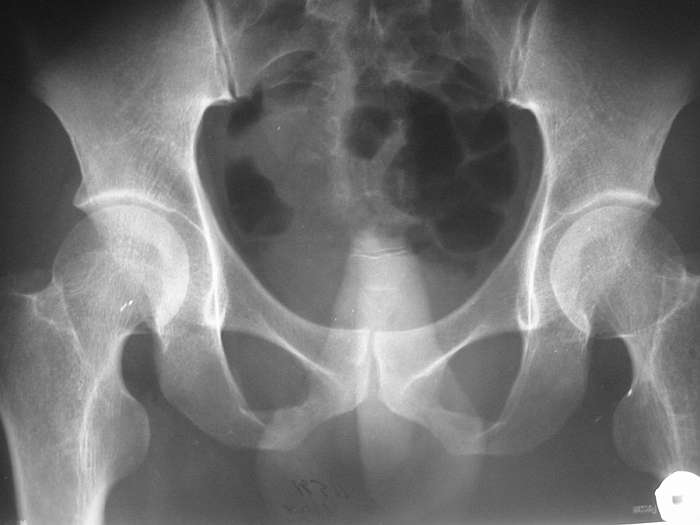

СА> P.S. хотелось бы увидеть снимок таза

Сегодня забегался и забыл про снимок, sorry. Завтра выложу.

ЗЫ: В приложении снимок таза.